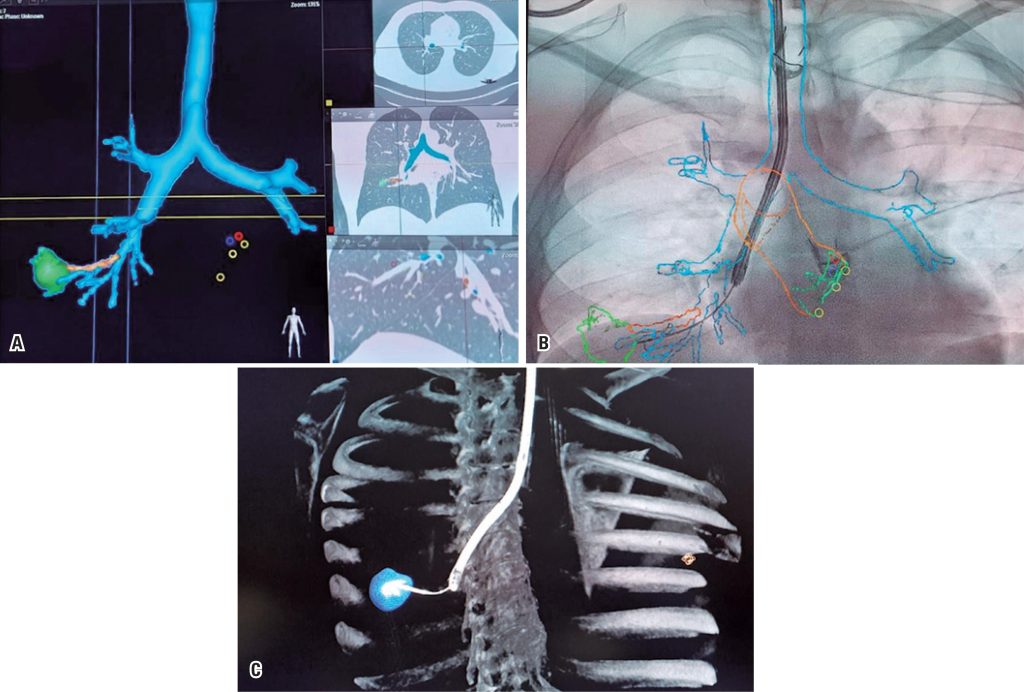

The article “Endobronchial ultrasound: minimally invasive technology to aid in the diagnosis of thoracic diseases”,() contributes to technical-diagnostic evolution of pulmonary lesions. Endobronchial ultrasound with a radial transducer enabled to perform cytopathological examination and transbronchial biopsy of small lung lesions. Bronchoscopic radial ultrasound and fluoroscopic images are usually combined procedures. The ability to target small peripheral lesions is technically complex due to the challenging localization of small airways in relation to lung lesions. For this reason, we began to perform the procedure in an interventional radiology suite, with the Philips Azurion angiograph by using image fusion software (Allura Clarity Philips, Netherlands) and cone beam tomography ( and ). In this way, we can perform roadmap navigation, and identify bronchial ramifications and the lesion ( to ). This technology allowed to reach smaller and more peripheral lesions, reduce radiation for patients and healthcare professionals, and make endobronchial intervention more accessible and less morbid.